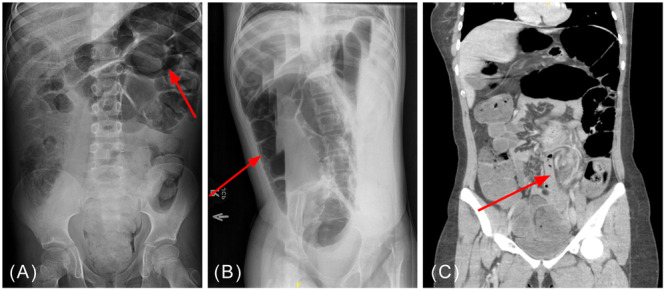

The process of the sigmoid colon twisting on its mesentery is known as sigmoid volvulus, a diagnosis rarely seen in the pediatric population. Volvulus can lead to blood flow obstruction of the colon and eventually perforation, necrosis, or sepsis. Predisposing factors include chronic constipation, chronic dysmotility, or Hirschsprung disease. This communication demonstrates three patients who presented to a tertiary pediatric care center with a diagnosis of sigmoid volvulus. All three patients underwent immediate endoscopic detorsion and rectal decompression tube placement. Two patients subsequently underwent surgical resection of redundant sigmoid colon. This communication highlights the use of sigmoidoscopy for detorsion of uncomplicated sigmoid volvulus with added support for initial rectal decompression tube placement, contributing to initial patient stabilization and positive patient outcomes.